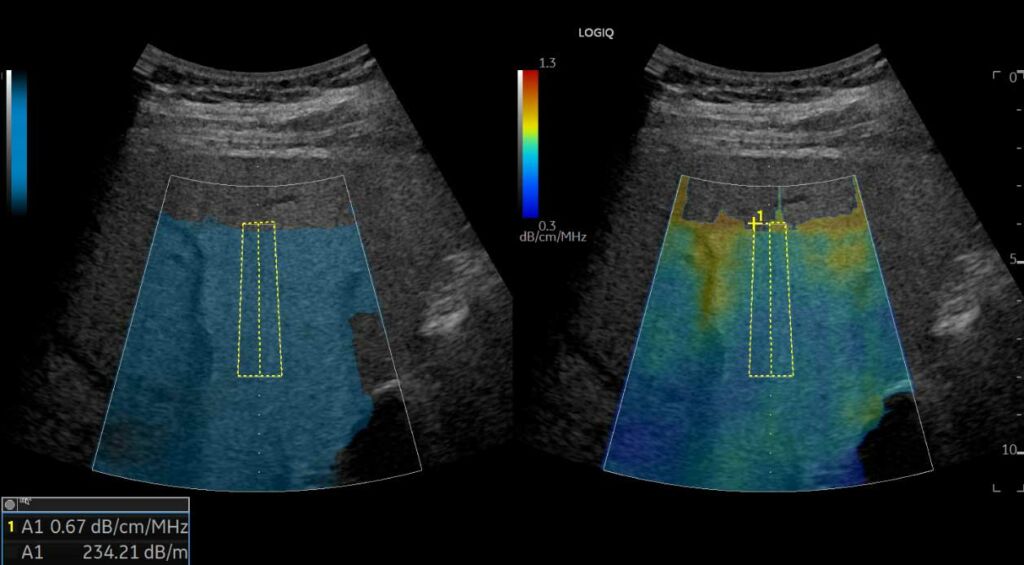

- UGAP (Ultrasound-Guided Attenuation Parameter), για την ποσοτικοποίηση της λιπώδους διήθησης του ήπατος. Οι δυνατότητες αυτές συμβάλλουν στην έγκαιρη αναγνώριση και παρακολούθηση ηπατικών παθήσεων όπως η ίνωση και η κίρρωση, που σχετίζονται με NAFLD(μη αλκοολική λιπώδη νόσο του ήπατος) NASH(μη αλκοολική στεατοηπατίτιδα) ή ASH(αλκοολική στεατοηπατίτιδα).